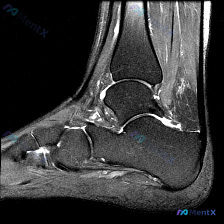

刚看到一个很有讨论价值的踝关节MRI读片病例,整理了一下资料和分析思路,跟大家分享。 病例影像基础信息 这是踝关节MRI-T2序列矢状位图像,核心问题是“影像中可以看到什么?提示软组织积液”。 先给大家整理影像所见: 1. 骨性结构:胫骨远端、距骨、跟骨、舟骨等结构显示清晰,骨髓信号整体正常,未见明...

病例影像读片分享 今天整理了一例踝关节MRI的读片资料,把分析思路分享给大家一起讨论。 基本影像信息 这是一张踝关节矢状位T2加权MRI,可以清晰显示胫骨远端、距骨、跟骨、舟骨、楔骨等踝关节复合体骨性结构,T2序列对液体信号显示清晰。 核心阳性发现 1. 多关节广泛积液:胫距关节前后隐窝、距下关节间...

最近看到一份踝关节MRI读片请求,问题是「影像中能观察到什么?提示软组织积液」,整理了完整的读片和分析思路,和大家分享讨论。 一、影像基本信息 这是踝关节矢状位MRI T2序列,影像观察结果如下: 1. 骨结构:胫骨远端、距骨、跟骨、舟骨、部分楔骨骨皮质轮廓完整,胫距关节间隙可见 2. 关节腔:胫距...

踝关节MRI读片病例分享,整理了完整分析思路 这是一例踝关节矢状位T2加权MRI,我把影像发现和分析思路整理出来,和大家一起讨论。 一、基本影像信息 这是踝关节MRI T2序列矢状位图像,可观察到胫骨远端、距骨、跟骨及周围软组织结构,核心阳性征象如下: 1. 骨骼关节改变:距骨穹窿(圆顶)可见明确局...

看到这个踝关节MRI的读片请求,问题是观察到的软组织积液,我整理了完整的影像和分析思路分享给大家。 病例影像基础信息 这是踝关节MRI矢状位T2序列图像,核心观察结果如下: 1. 骨骼系统:胫骨远端、距骨、跟骨、舟骨骨皮质完整,未见明确骨折线;距骨体及跟骨骨髓信号均匀,无明显水肿或硬化改变 2. 关...

今天给大家分享一张踝关节MRI矢状位T2加权影像的读片分析,病例本身并不复杂,但这种仅表现为少量积液的情况,临床其实很容易走偏,整理一下完整的思考过程给大家参考。 一、影像核心信息整理 这张是踝关节矢状位T2加权MRI,我们先把所有明确的影像信息理清楚: 1. 骨骼结构:胫骨远端、距骨、跟骨、舟骨骨...

看到一份很有代表性的踝关节MRI影像,整理了资料和分析思路分享给大家。 病例影像基本信息 这是一份踝关节矢状位T2加权像(T2WI),先给大家说下客观观察到的结果: 1. 解剖结构显示清晰:可以看到胫骨远端、距骨、跟骨、足舟骨及部分跖骨 2. 核心异常发现: - 胫距关节腔前方、后方可见明显T2高信...

最近看到这例踝关节MRI读片讨论,问题是「图像中能观察到什么软组织液相关改变」,整理一下完整分析思路,分享给大家。 一、病例影像核心信息 这是踝关节MRI冠状位T2加权图像,核心发现如下: 1. 骨结构改变:胫骨远端、距骨、跟骨显影清晰,距骨穹窿内侧关节面可见局灶性高信号改变,边界清晰,呈楔形凹陷状...